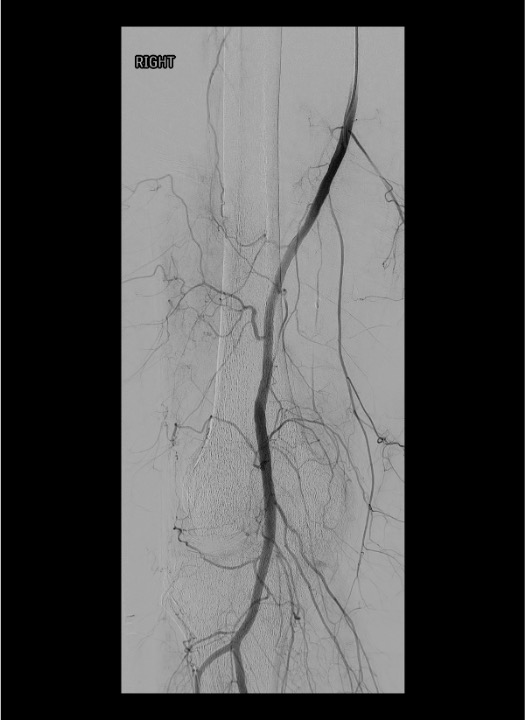

Normal vs. Pathologic Arteriogram

- Normal: Thin, well-defined genicular branches; minimal parenchymal blush in periarticular soft tissues

- OA/synovitis: Markedly increased neovessels; dense, persistent, diffuse synovial blush (hyperemia) — especially in medial and anterior compartments

- Post-arthroplasty hemarthrosis: Focal hypertrophic synovial neovessels, often superomedial distribution

- Compare affected knee arteriogram to published normal anatomy (Fig. 36.4 in source text) — the contrast is striking in symptomatic patients

Popliteal arteriogram — map genicular anatomy

Superselective catheterization with microcatheter

Pre-embolization test injection

Post-embolization popliteal arteriogram

Vessel Identification on DSA

- Popliteal artery: Centerline vessel in the posterior knee; all geniculars arise from it within ~5 cm above and below joint line

- SMGA / SLGA: Arise 3–5 cm above joint line; curve medially or laterally around respective femoral condyles; visible on AP and oblique views

- IMGA / ILGA: Arise at or just below the joint line; smaller caliber; often multiple branches; best seen on oblique views (30–45°)

- Middle genicular: Short posterior branch; may not be selectively catheterized; contributes less to anterior synovial hyperemia

- Use oblique views (30–45° ipsilateral and contralateral) to separate overlapping vessel takeoffs and open the orifices of individual genicular arteries

Identifying Target vs. Non-Target Blush

- Pathologic synovial blush (target): Persistent, diffuse, hazy enhancement in medial or anterior knee compartment = neovascular hyperemia; inject here

- Normal parenchymal stain: Thin, transient enhancement that clears quickly — not a clear blush

- Skin / subcutaneous blush (danger): Enhancement near tibial tubercle, infrapatellar region, or lateral skin — stop immediately; this is Hoffa fat pad or cutaneous supply; embolization here causes skin necrosis